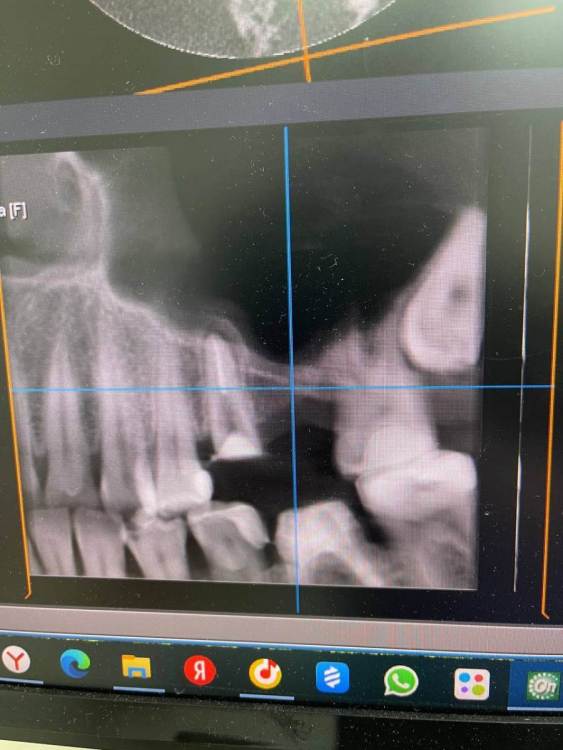

TIGER Опубликовано 8 мая, 2023 Автор Поделиться Опубликовано 8 мая, 2023 Всем привет!планировал удаление,но во время синуса решил использовать фрагмент как клин для стабилизации болта,в итоге совершил ошибку с более медиальной позицией 26,ибо шаблон не изготовил....через 5 мес одел времяхи,т.к будет тотал Ссылка на комментарий

Irouil Опубликовано 8 мая, 2023 Поделиться Опубликовано 8 мая, 2023 Вроде норм, в итоге 1 Ссылка на комментарий

TIGER Опубликовано 8 мая, 2023 Автор Поделиться Опубликовано 8 мая, 2023 @Irouil да,ортопедически всё отлично,я переживал Ссылка на комментарий